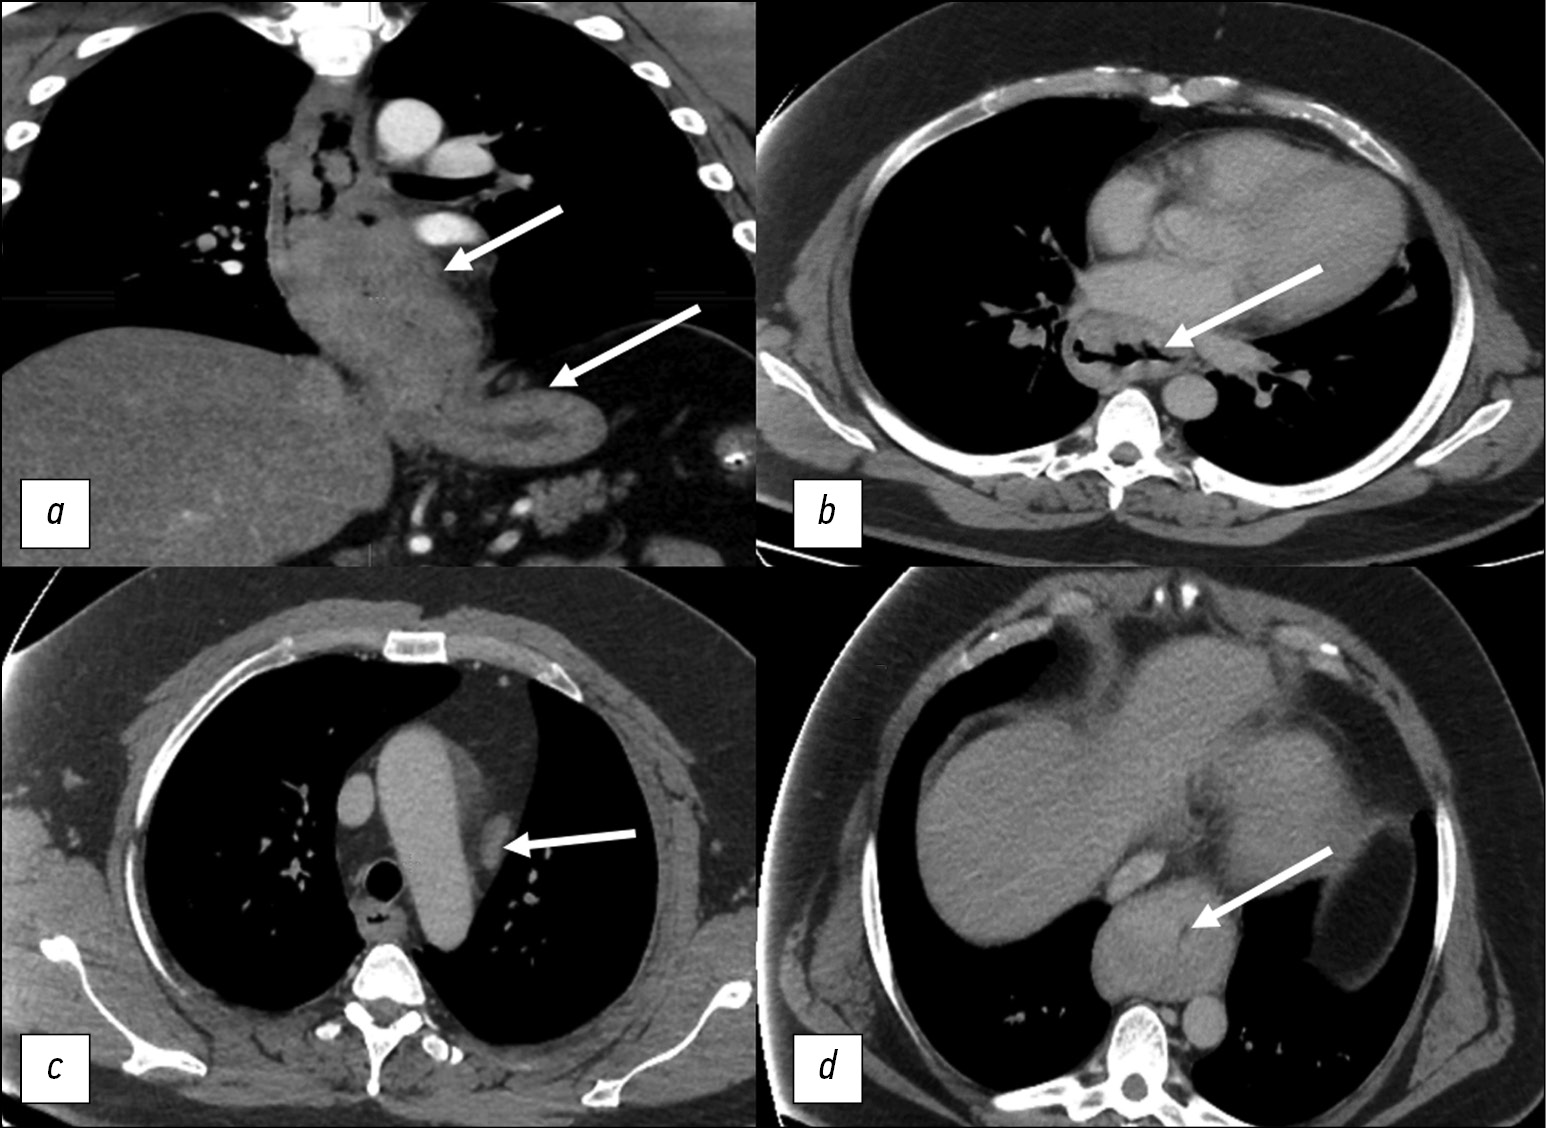

Chest CT showed a 186-mm esophageal tumor that had extended to the cardia. The esophageal walls had a polypoid thickening of up to 41 mm, and a significant narrowing of the esophageal lumen to 2 mm was observed. Signs of regional lymph node involvement were also visible (Fig. 2).

Fig. 2. Computed tomography of the chest organs. White arrows indicate pathological changes: a — neoplasm of the esophagus, spreading to the cardia of the stomach, 186 mm long; b - massive proliferation of tumor tissue with narrowing of the lumen in the middle third of the esophagus; c — tumor lesion of the regional para-aortic lymph node; d — narrowing of the lumen of the esophagus to 2 mm in the lower third.